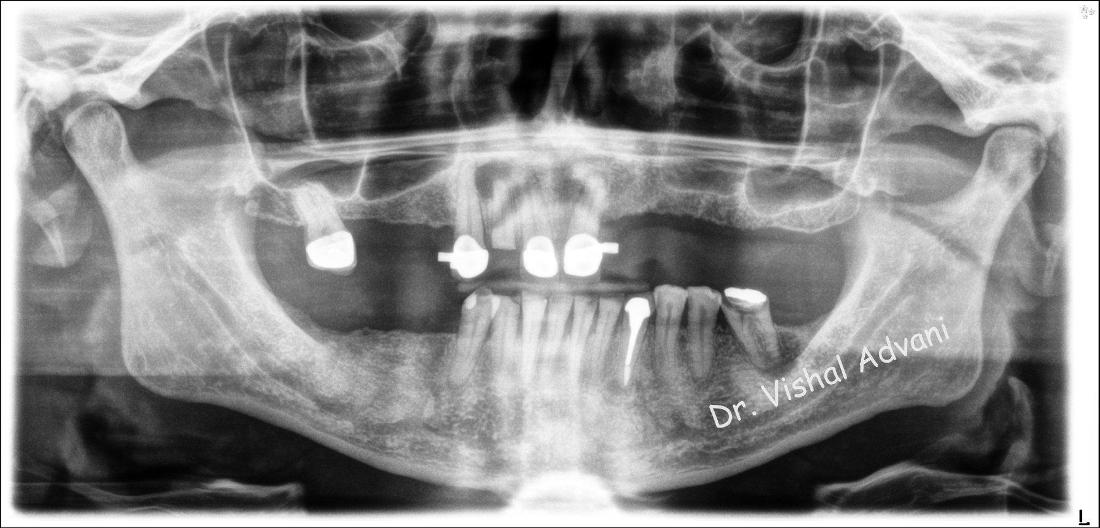

This patient only had a few broken and infected remaining teeth on the top and had trouble eating and speaking.  He didn't feel comfortable smiling due to the missing teeth. He wanted a permanent solution to replace the missing teeth.

The broken and infected front teeth were removed and 5 implants were placed by Dr. Vishal Advani. The patient left with a screwed-down, attached bridge.  The entire procedure was completed in less than 3 years, which included removing the broken teeth, the placement of 5 dental implants and attached a temporary bridge.  All the steps were completed by Dr. Vishal Advani in one location.

The patient asked for a darker color for his bridge to give him a more age-appropriate, natural look.